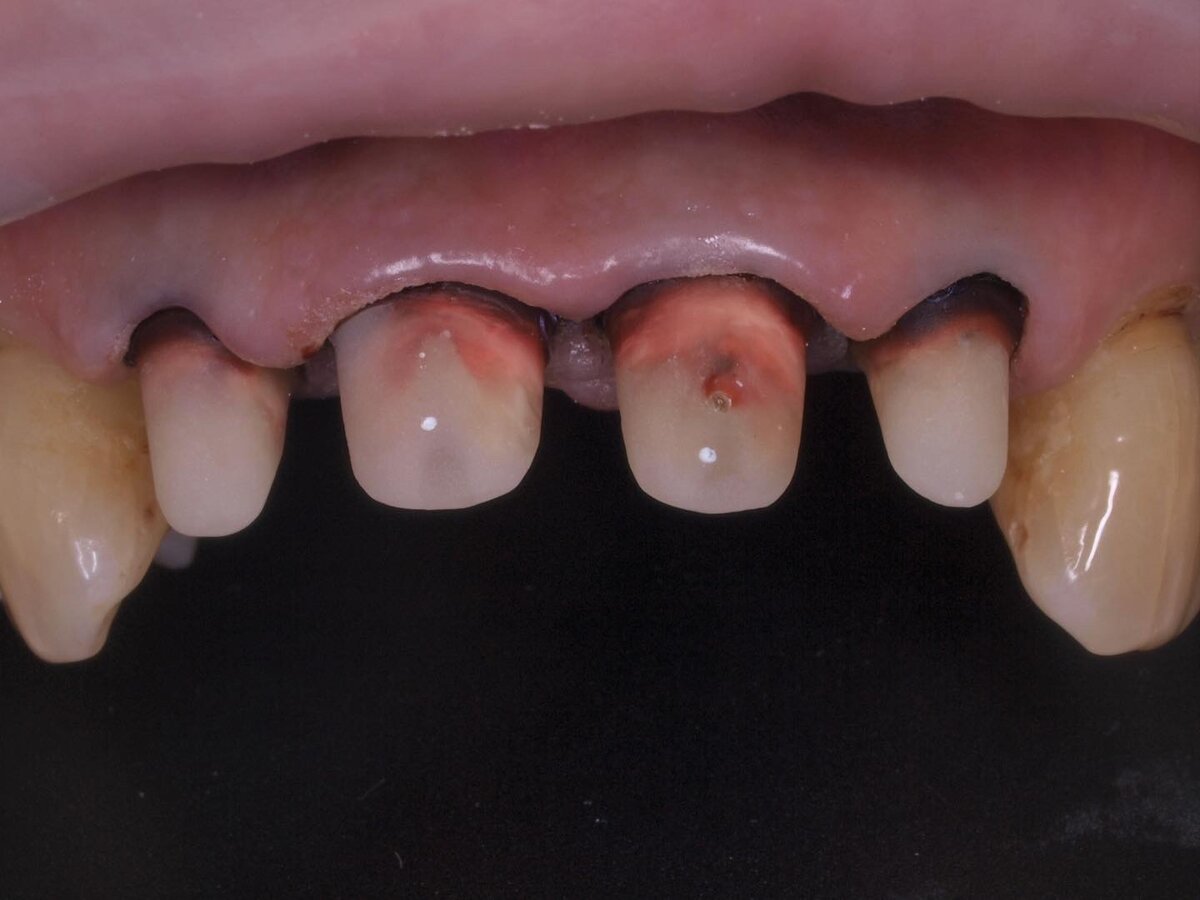

В данном клиническом случае представлена металлокерамическая конструкция из 4 объединённых коронок на 4 передних зуба верхней челюсти. У пациентки уже была такая конструкция прежде, и замена производилась в связи со сколом керамической облицовки. Мы лишь повторили и обновили ее.

Зубы подготовлены для фиксации коронок